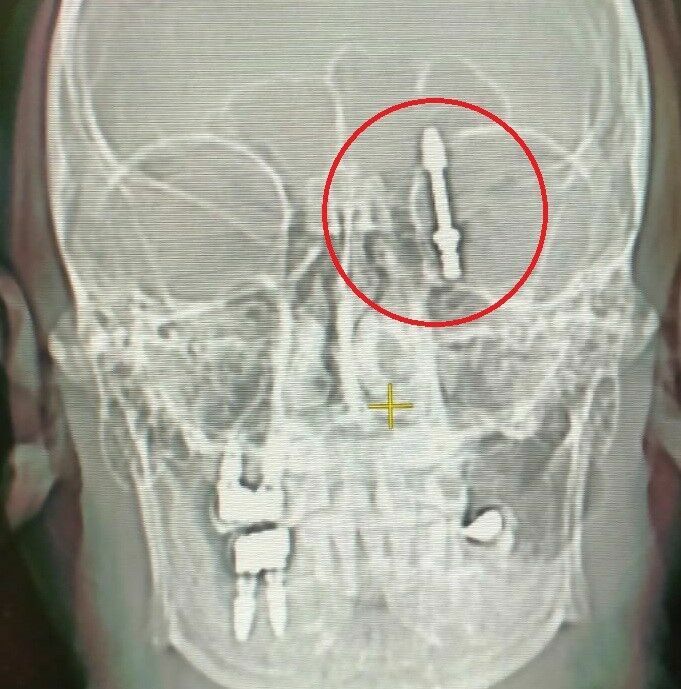

Fabrika işçisi Ramazan Yılmaz'ın (40) sızı yapan dişlerinin tedavisi için gittiği klinikte, doktorun yanlış müdahalesiyle yaşanan kaza sonucunda vida, çene kemiğini delip hastanın beynine saplandı.

Yılmaz'ın anlatımına göre, implant operasyonu sırasında doktorun müdahalesinde kullanılan cihazın bozuk olması üzerine yaşanan bir dizi hata sonucunda korkunç bir olay meydana geldi. Doktor, vida yerleştirmeye çalışırken aşırı yüklenince, Yılmaz bu durumu fark ederek uyardı. Ancak doktor, uyarıları dikkate almadı ve işlemi sürdürdü. Sonuç olarak, vida çene kemiğini delip beyin omurilik sıvısının bulunduğu bölgeye saplandı.

Ameliyat sonrasında sağlığına kavuşan Yılmaz, yaşadığı mağduriyetin giderilmediğini ve doktorun kendisine karşı sorumluluklarını yerine getirmediğini belirtti. İkinci bir şok yaşayan Yılmaz, adaletin yerini bulması için hukuki süreci başlattı ve doktordan şikayetçi oldu. Yılmaz, 'Dişlerimde oluşan rahatsızlık sonrası Nilüfer'de bulunan özel bir diş kliniğine gittim. Orada yapılan incelemeler sonucunda kemik yapımın ince olduğunu, dişlerimin sallandığını ve implant yapılmasını yönünde işlem olacağı hakkında bilgi aldım. Doktor bana kendisinin 24 yıllık hekim olduğunu ve bu alanda uzman olduğunu söyledi. Biz de kendisine güvenerek bu işi ona bıraktık. Daha sonra dişlerimi çekip, aynı gün implant uygulaması yaparken, işlemde kullandığı cihazın bozuk olduğunu sekreterine söyledi. Bu kez de işlemi eliyle yapmaya başladı. Vidayı yerleştirmeye çalışırken, aşırı yüklendiğini fark ettim. Bunu kendisine söyledim, kemik sesi geldiğini ifade ettim. Fakat bu kez de bana bunun normal olduğunu söyledi. Ama vidayı zorlarken, vida çene kemiğimi delip göz duvarının arkasından beyin omurilik sıvısının olduğu bölgeye saplandı. Ben acıdan dolayı bağırınca röntgen çektirdi. Durumun ciddiyetini anlayınca beni Uludağ Üniversitesi Hastanesinin Acil bölümüne getirip gitti. Burada yapılan inceleme sonrası vidanın beyin omurilik sıvısının olduğu yere saplandığı görüldü. Daha sonra uzman hekimler bir araya gelip, ameliyat için karar aldılar. Ameliyat öncesi bana hayatımı kaybedebileceğimi söylediler. Ben artık çocuklarımla helalleşip vedalaştım. Çok şükür ameliyattan sağ salim çıktım. Bu süreçlerde diş hekimi hiç bir zaman yanımda olup mağduriyetimi gidermedi, hatta ödediğim ücreti dahi geri iade etmedi. Üstüne üstelik benimle dalga geçer gibi konuştu. Bunların hepsi belgeli. Ben yetkililerden devlet büyüklerimizden bu konuyla ilgilenilmesini istiyorum. Benim iki çocuğum var. Bana bir şey olsaydı bunların hesabını kim verecekti ? Şimdi dava sürecine girdik. Kendisinden şikayetçi oldum' dedi.